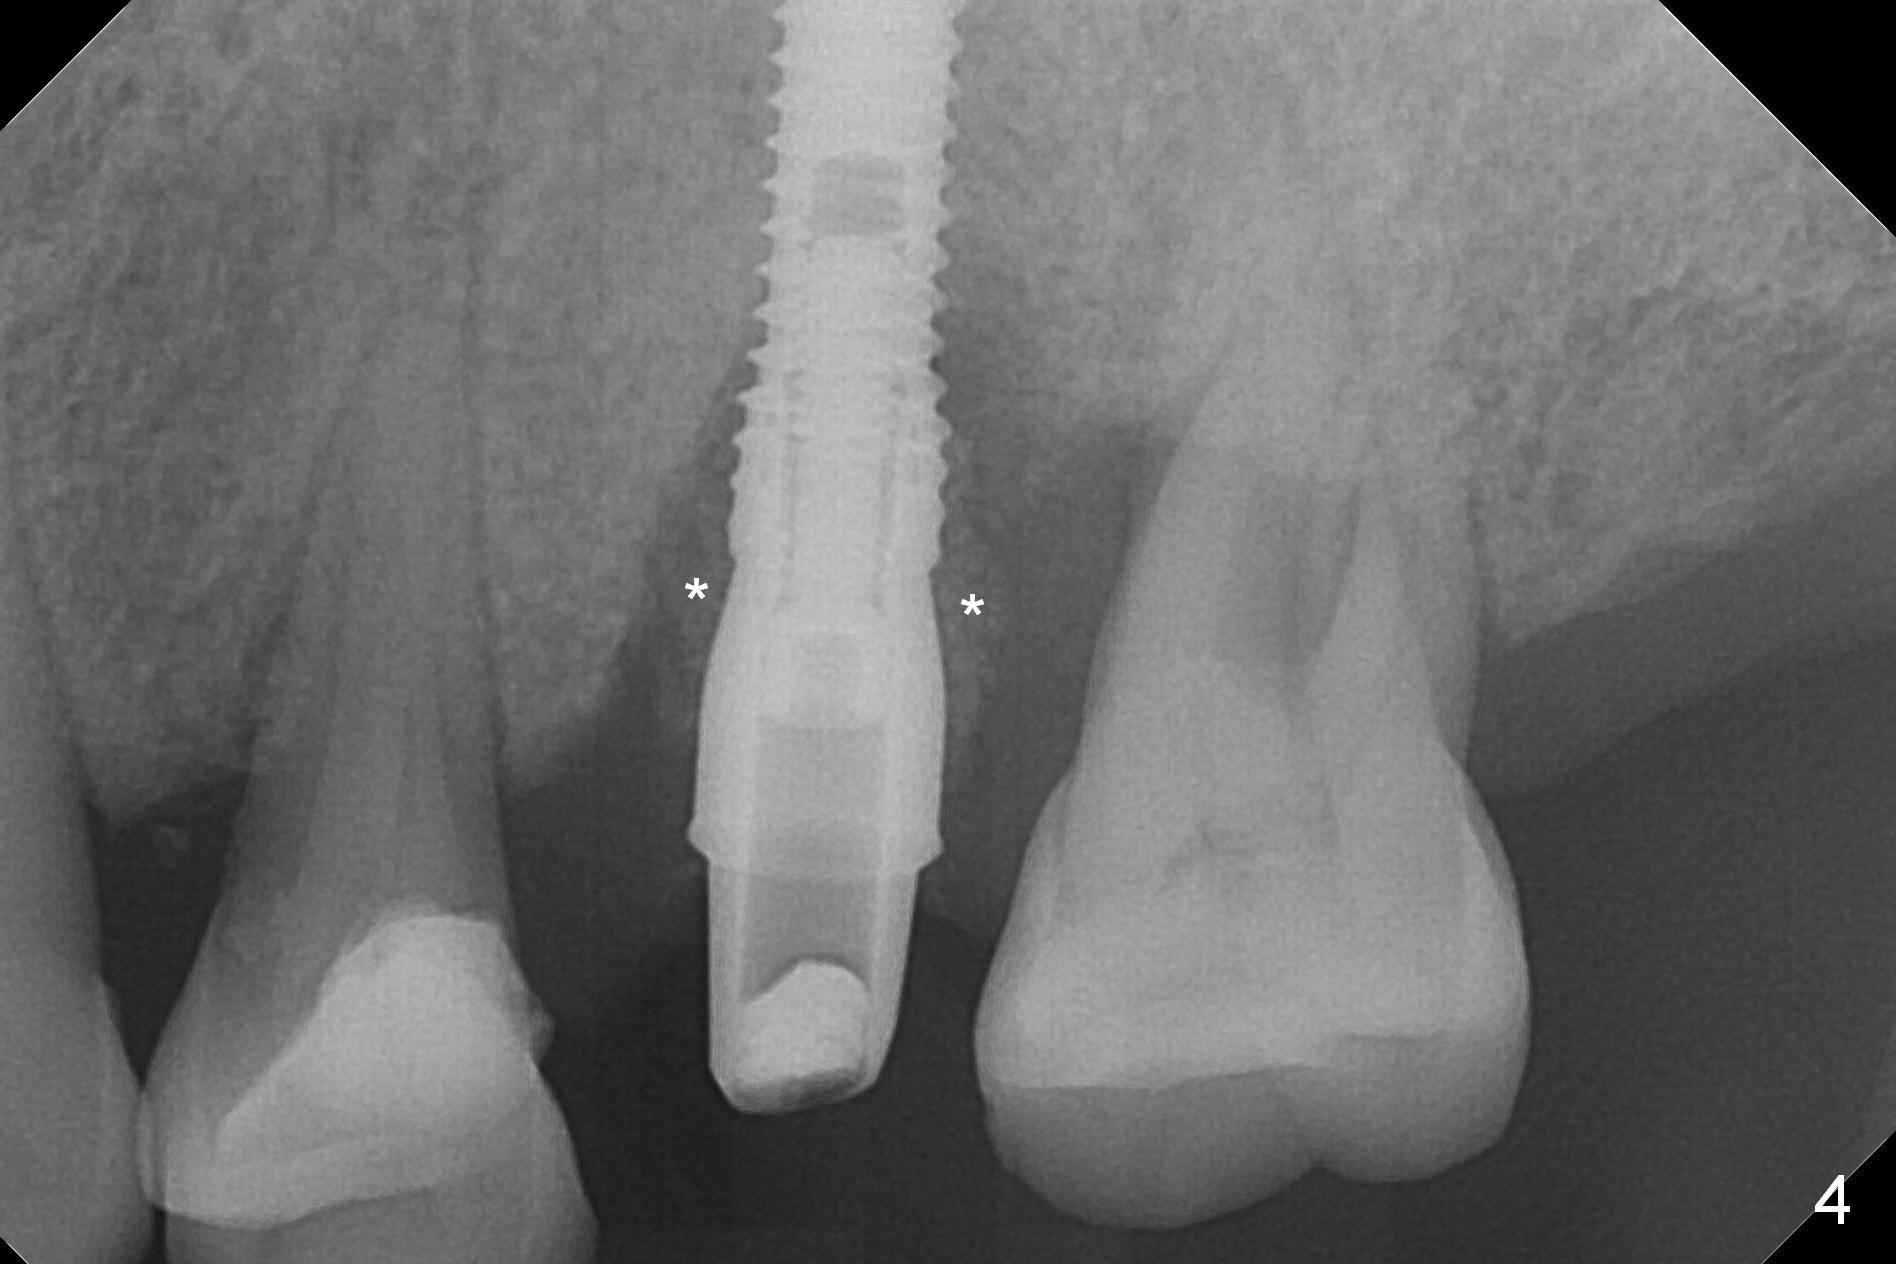

Initial osteotomy depth is 18 mm (Fig.1 green line) with 9 mm in the native bone (red line).  The bone density feels to be low.  There is at least 2 more mm bone apically (pink line).  The depth is increased by 2 mm so that when a 3.8x15 mm implant is placed, there is 10-11 mm implant/bone contact (Fig.2 red line).  There is large bony defect (Fig.3 *), which is bone grafted (Fig.4 *).  Finally a longer abutment is placed (4.5x5.5(5) in Fig.4 vs. 4.5x4(5) in Fig.2,3).  The 5 mm cuff does not look too long buccally (Fig.5) or palatally (Fig.6).   To prevent postop buccal gingival overgrowth (2), the buccal margin of an immediate provisional is subgingival (Fig.7-9 *).  Bone density between #13 and 14 appears to increase 3 months postop (Fig.10).  The implant seems to be equi-crestal (Fig.11 ^).  There seems to be more bone growth (i.e., decreasing gap) 6 months postop (Fig.12).  Impression is taken.  A crown is delivered nearly 7 months postop (08/07/2017).   While there is minimal bone loss at #13 and 15 three years and 4 months post cementation, the tooth #14 and 18 are mobile (Fig.13,14).